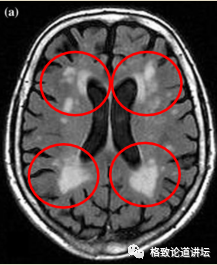

我们能看到这个图大脑前边在侧脑室前后角有两块白的东西,这是白质脱髓鞘,我们也叫“穿靴戴帽”,非常形象。这预示着那部分白质的损害,使得脑的环路受到了影响。人的情感环路实际上是有神经结构支持的。老年的这种情感环路的损害就会造成抑郁,所以老年期的抑郁是有病理基础的。